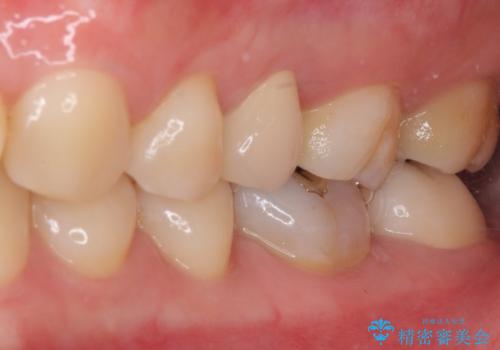

奥歯が痛い 保険治療後に症状が発現した歯のむし歯治療

- 近医にてむし歯治療を行った後に痛みが出たとのことで来院された患者様です。

左下奥歯は術後から咬合時の痛みが発現し、来院時には脈を打つような痛みが認められました。

診察の結果、神経を取り除く必要があると判断されたため根管治療を行いました。

その後、左上の奥歯にも咬合時の痛みが認められ、レントゲン写真より歯内の神経が失活していることが分かりました。

2歯ともに根管治療を行い、その後はオールセラミッククラウンにて補綴治療を行うこととしました。

来院時には食事が取れないほどの痛みを訴えていらっしゃいましたが、処置後からは痛みが軽減され、食事もいつも通りに取れるようになりました。